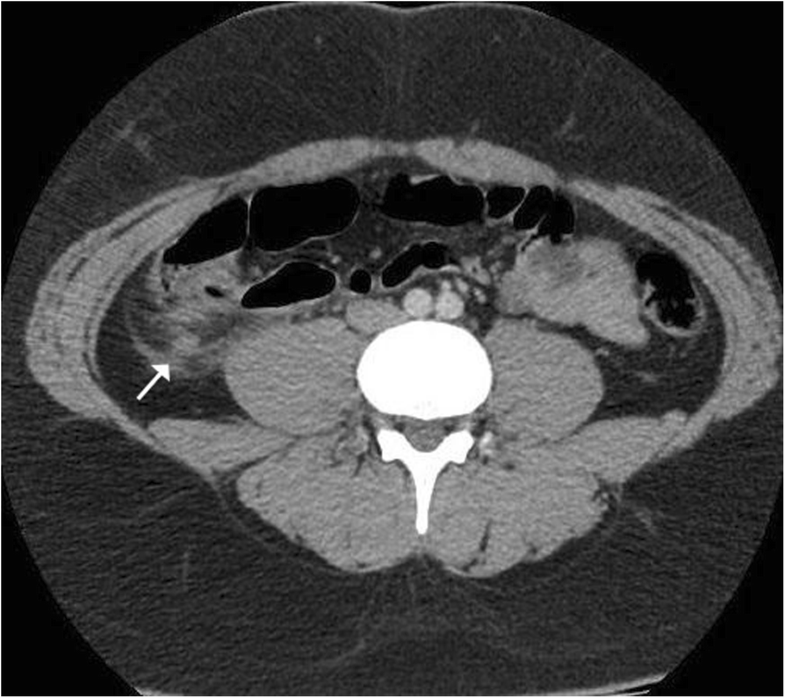

From www.researchgate.net

Arrow indicating appendiceal stump with inflammatory changes What Is An Inverted Appendiceal Stump Stump appendicitis is defined by the recurrent inflammation of the residual appendix after the appendix has been only partially removed. Stump appendicitis refers to inflammation of the residual appendiceal tissue post appendectomy. Appendiceal inversion (ai) describes an appendix that is pulled into the lumen of the cecum. Appendiceal inversion is an uncommon entity that presents a diagnostic dilemma for the. What Is An Inverted Appendiceal Stump.